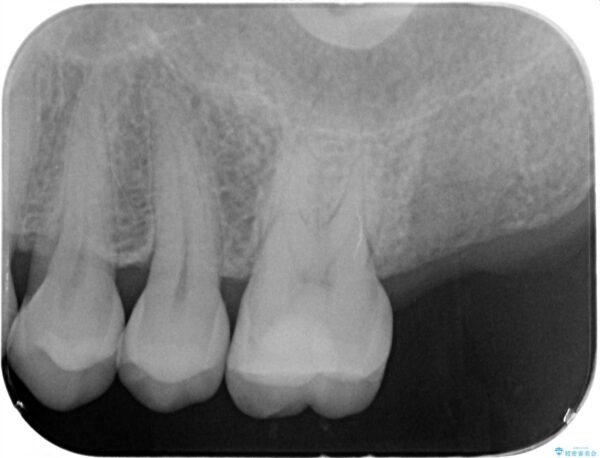

精査した結果、上顎奥歯は歯が割れてしまっており、根管治療ではなく抜歯の対象でした。

治療前

【噛むと歯が疼く】歯牙破折からのインプラント治療 治療前画像 【噛むと歯が疼く】歯牙破折からのインプラント治療 治療前画像 【噛むと歯が疼く】歯牙破折からのインプラント治療 治療前画像 【噛むと歯が疼く】歯牙破折からのインプラント治療 治療前画像 【噛むと歯が疼く】歯牙破折からのインプラント治療 治療前画像 【噛むと歯が疼く】歯牙破折からのインプラント治療 治療前画像 【噛むと歯が疼く】歯牙破折からのインプラント治療 治療前画像